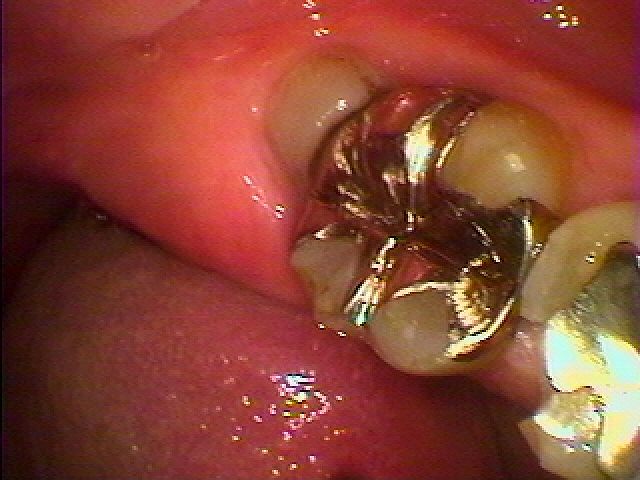

わずかに見える親知らずになります

親知らずを抜く日に銀歯が外れてきました

歯冠部を分割していきました

その後根を取り出しています

切開はしないです